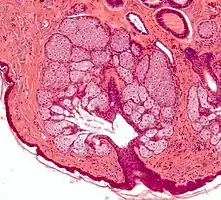

Les glandes sébacés ont une architecture acinaire (comme une grappe de raisin) et n'ont pas de lumières propre. Elles sont composés de sébocytes matures, dont la sécrétion est le résultat de leur mort par apoptose, ce qui revient à une sécrétion holocrine. Le remplacement des cellules est assuré par les cellules de la matrice reposant sur la membrane basale[5].L'annexe pilo-sébacée constituée du follicule pileux, des glandes sébacés et des muscles arrecteurs du poils, résulte d'une invagination épithéliale[4].

Annexe pilosébacée avec glandes sébacés s'abouchant à un follicule pileux.

Multiples glandes sébacés s'abouchant à un follicule pileux.